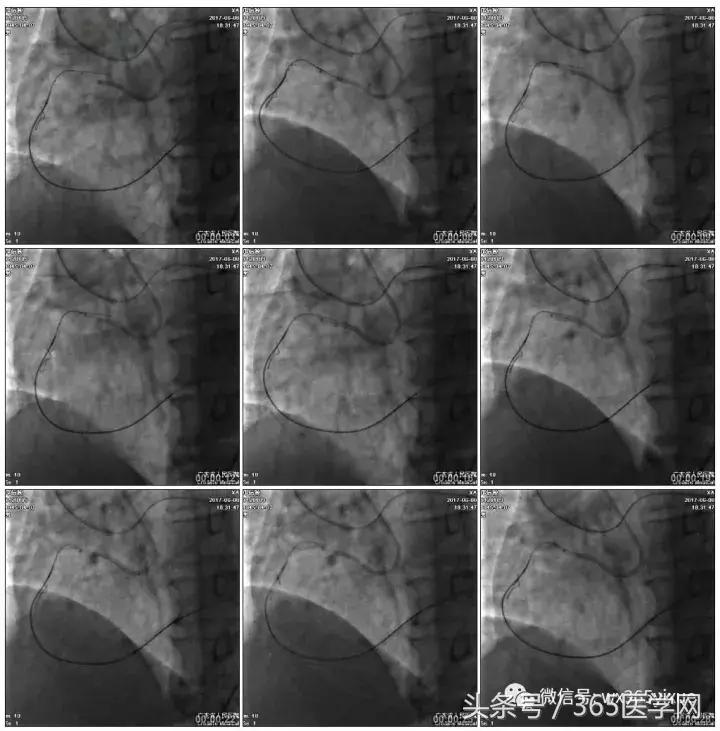

正向浅尝,改为逆向,LCX-PL

RRA:6F AL0.75 GC –RCA;

RFA:7F XB 3.5 GC—LCA 150cmcorsair

正向130cmFinecross微导管支持下尝试送PILOT150、Gaia 2导丝无法通过RCA闭塞段

SION导丝通过侧枝

逆向导丝:更换Gaia2

正向导丝:Gaia2,PILT150

正向导丝knuckle

2.5*15mm球囊扩张,逆向导丝尝试,但未能进入正向GC

1.正向2.5*15mm球囊扩张,Reverse CART

2.Guidezilla延长导管辅助下,逆向导丝进入正向GC

1.更换RG3导丝

2.GC送入普通导丝,保护LM